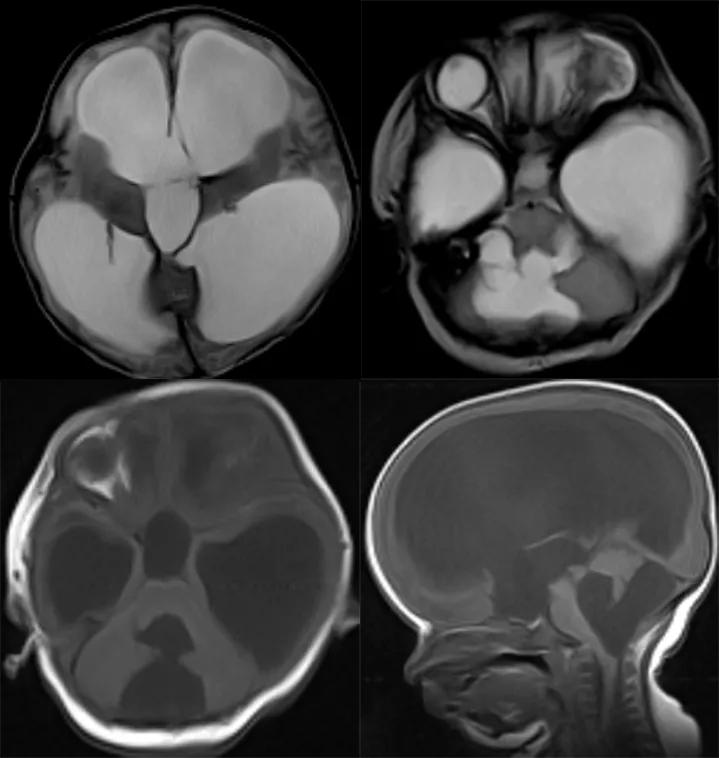

Dandy-Walker 综合征

Dandy-Walker 综合征(Dandy-Walker Syndrone DWS)又叫第四脑室孔闭塞综合征,是一种后颅窝先天发育畸形,是一种较罕见的颅脑先天发育异常

典型表现包括:小脑发育异常或蚓部缺失,小脑半球分离;‚第四脑室扩大并与后颅窝贯通,伴有横窦、窦汇及小脑幕上移;ƒ幕上脑室对称性扩张

case 1:男性,11 个月 10 天。突发呼吸急促、*吟呻** 8 小时

诊断:Dandy-Walker 综合征。